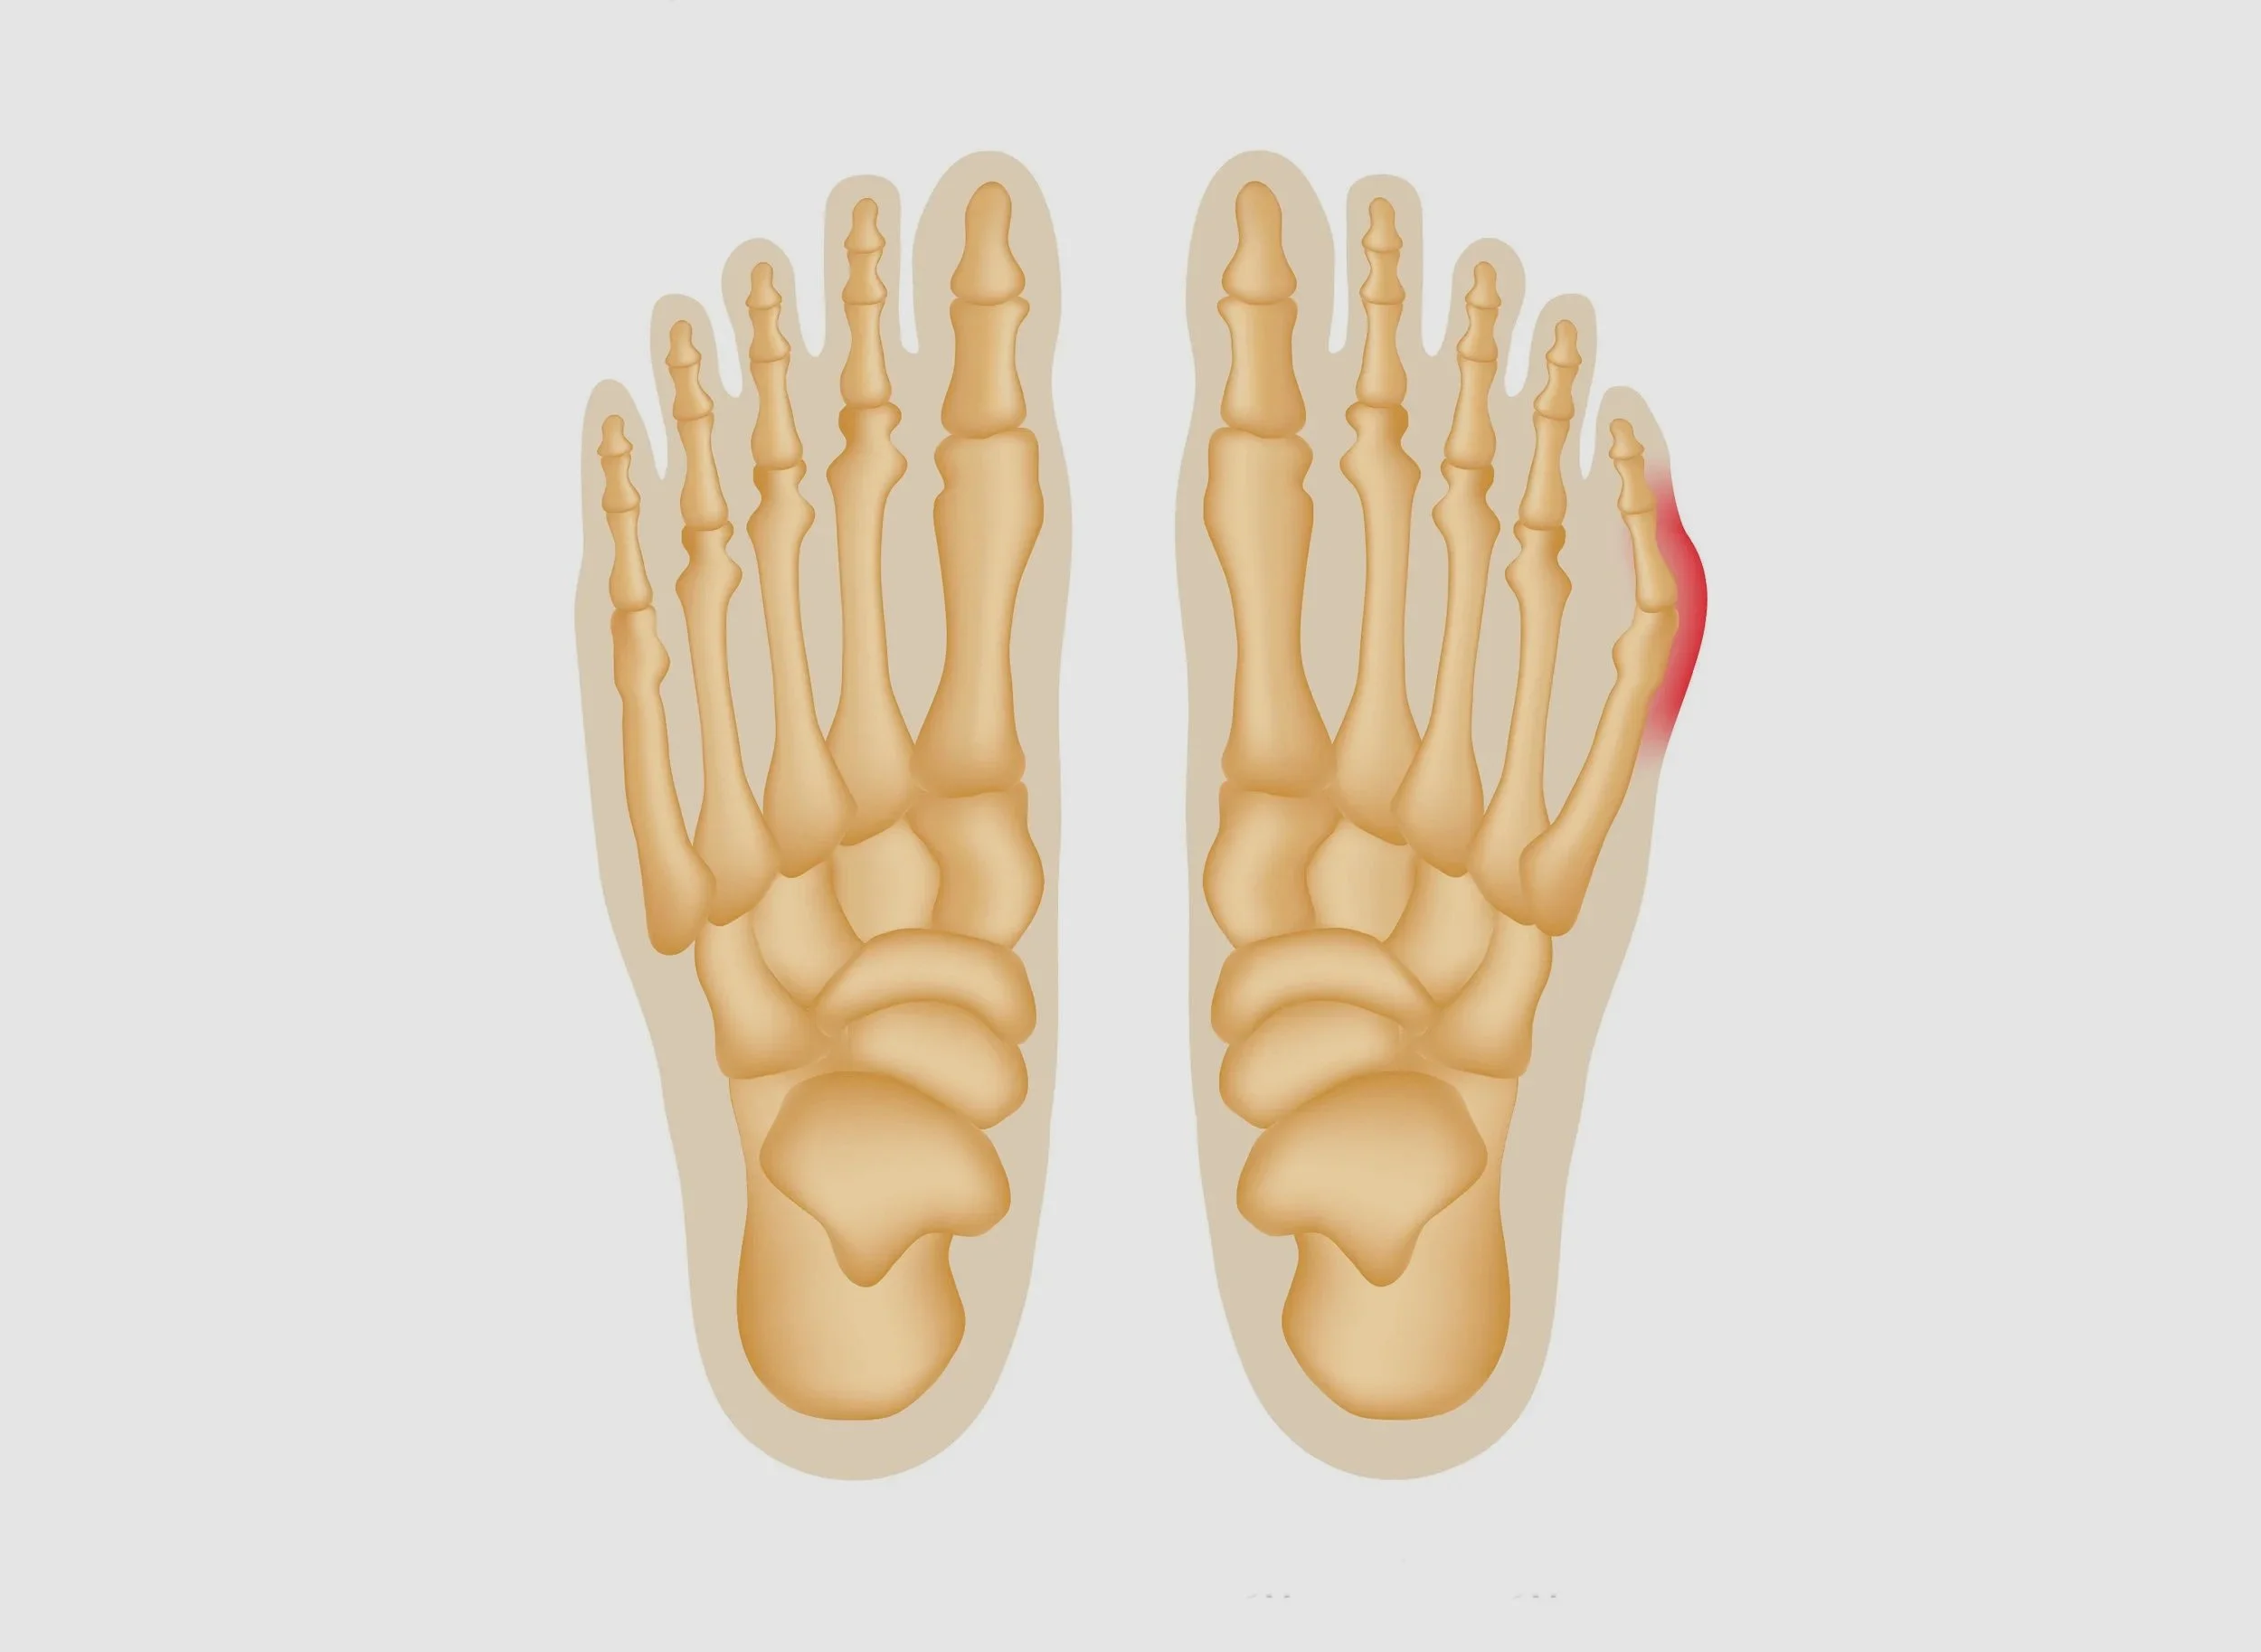

Tailor's Bunion

Tailor's Bunion Surgery (Osteotomy)

Your little toe has turned towards your fourth toe causing a bony bump to stick out at the side of your foot.  Read more >>